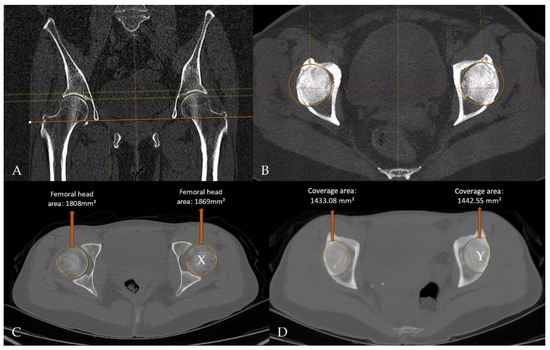

Figure 5.

CT- and MIP-derived images illustrate quantitative assessment of femoral head morphology and acetabular coverage on a radiology workstation. (A,B) Axial MIP reformats aligned using the teardrop landmarks, demonstrating CT-MIP processing on the imaging workstation. (C) Maximal femoral head cross-sectional area measured on axial CT images. (D) Acetabular coverage area segmented on multiplanar MIP reconstructions. The acetabular coverage index was calculated as Y/X (right, 0.792632; left, 0.771829).